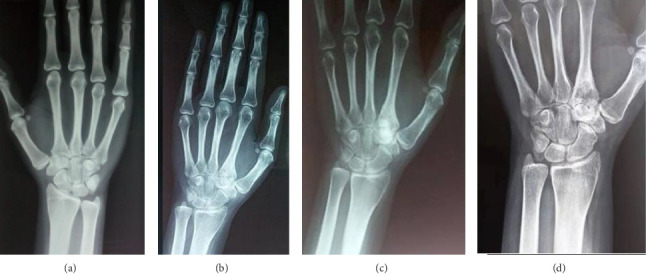

Osteoid osteomas predominantly occur in the cortices of long bones, with the femur and tibia being the most commonly affected sites. However, they can occasionally present in atypical locations, such as the carpus, which can lead to diagnostic confusion with other conditions. This case report details an intraarticular osteoid osteoma in the trapezoid bone. Initial evaluations, including standard radiographs, joint ultrasound, and wrist MRI performed twice, initially pointed toward a diagnosis of wrist synovitis. This case underscores the diagnostic challenges posed by atypical presentations of osteoid osteomas. Given the edema present in the carpal bones alongside the synovitis, we performed a hand CT scan, which raised doubts about the appearance of the nidus and histopathological examination confirmed the diagnosis. Clinical symptoms, including pain and functional limitations, were completely resolved following surgical excision.